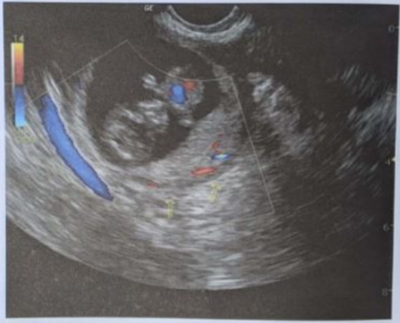

Jovem de 15 anos chega ao serviço de urgência com queixa de dor abdominal aguda em hipogástrio, que se iniciou após atividade sexual. Usa DIU de cobre e está no 14° dia do ciclo menstrual. Está apresentando náuseas e tontura no momento. PA = 100 x 60 mmHg, FC = 108 bpm. Fez teste de gravidez negativo, Hemoglobina = 10,2 g/dL. A ultrassonografia de pelve e abdome observou pequena quantidade de líquido ecogênico intraperitoneal e uma massa em projeção de anexo direito com 5 cm de diâmetro e as demais características abaixo. A hipótese diagnóstica mais provável é